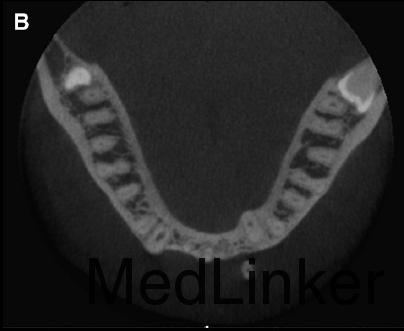

舌侧丝保持器在右侧侧切牙与尖牙间被破坏,右侧中切牙与侧切牙舌向移动,而左侧尖牙唇向移动。下颌运动过程中,左下2承受了切导的全部负荷。左下2活力测试显示无活力。CT矢状向显示32牙完全位于骨皮质外,32牙根尖1/3横断面显示牙根周围无骨质包绕